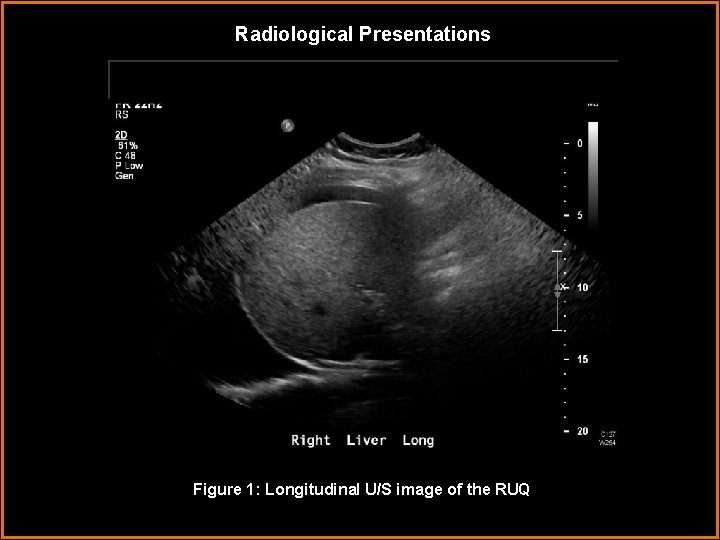

Radiological Presentations Figure 1: Longitudinal U/S image of the RUQL

Findings and Differentials Findings: - Abdominal U/S images demonstrate moderate to large amount of ascites. The images of the right and left upper quadrants also show bilateral pleural effusions. - Transabdominal images of the pelvis also show ascites. The endometrium is diffusely echogenic and thickened to over 2 cm, consistent with a secretory phase appearance. - The ovaries are both grossly enlarged, containing multiple large peripheral anechoic areas with thin walls, consistent with simple cysts. The right ovary measures 14. 6 x 9. 7 x 12. 8 cm and the left ovary measures 11. 3 x 11. 9 x 12. 1 cm. The ovarian stroma is normal in echogenicity with flow demonstrated on Doppler bilaterally.